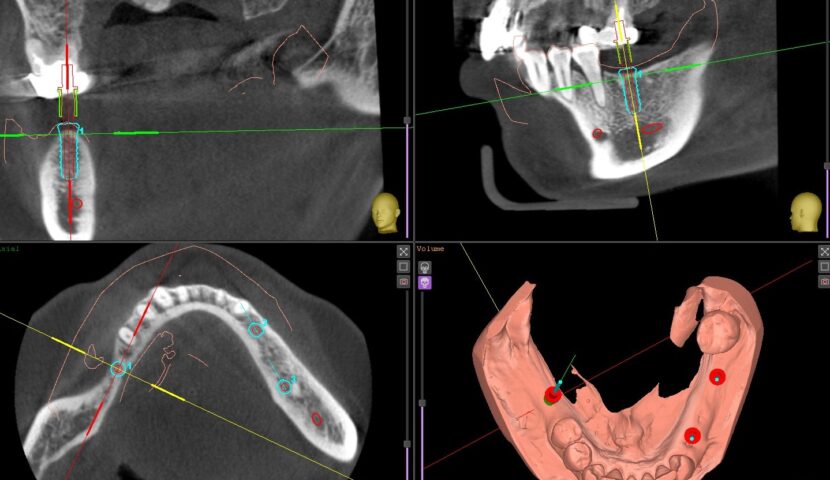

インプラント症例その8

インプラント症例その7